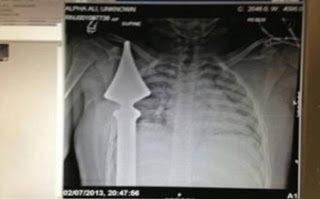

Ζει από θαύμα: Μαθητής καρφώθηκε σε μεταλλικό φράχτη

Από του Χάρου τα δόντια γλίτωσε ένα αγόρι 12 ετών, όταν καρφώθηκε επάνω σε μεταλλικό φράχτη ενώ έπαιζε κοντά στο σπίτι του στο Essex.

Ο Josh Hassan έχασε την ισορροπία του ενώ προσπαθούσε να πιάσει τη μπάλα του, όπως διαβάσαμε στο gamato και βρέθηκε με ένα σίδερο καρφωμένο στην περιοχή του στήθους, μερικά εκατοστά μακριά από την καρδιά του.